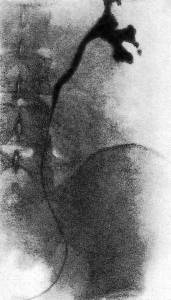

• болезнь Ормонда - фотоИнструментальные методы. На обзорной рентгенограмме почек и верхних мочевыводящих путей определяют расплывчатость контуров поясничной мышцы и очертаний почек. Экскреторная урография позволяет выявить длинные суженные участки мочеточника и его медиальное отклонение в проекции средней трети, а также гидронефронефротическую трансформацию и характерные изменения мочеточников — расширение до среднего физиологического сужения (обструкция за счёт сдавления извне) со смещением в медиальную сторону. Аналогичную картину выявляет ретроградная пиелоуретерография. Тем не менее, при РПФ медиальное отклонение возникает не всегда, в то время как у 20% людей с нормальными мочевыводящими путями также выявляют данное отклонение мочеточников. Таким образом, по данным уретеропиелограмм, триада, указывающая на наличие болезни Ормонда, включает:

• гидронефроз с расширенным извилистым верхним сегментом мочеточника;

• медиальную девиацию мочеточника;

• наружную компрессию мочеточника.

При невозможности выполнения ретроградной производят чрезкожную антеградную пиелоуретерографию. С помощью радиоинуклидного исследования оценивают функциональное состояние почек и верхних мочевыводящих путей. Ультразвуковое исследование подвздошных сосудов с цветным допплеровским картированием подтверждает расширение полости почки и мочеточника и выявляет прерывание мочеточника на уровне его перекреста с подвздошными сосудами. Определенное диагностическое значение имеет венокаваграфия. Для заболевания характерны сужение или обструкция нижней полой вены с развитием коллатералей, а также смещение её поясничного отдела кпереди. В последнее время для диагностики РПФ используют КТ и МРТ. Данные виды медицинского обследования позволяют выявить не только расширение верхних мочевыводящих путей, но и однородное объёмное образование, окружающее мочеточник, нижнюю полую вену и аорту. Учитывая, что ретроперитонеальный фиброз может возникнуть вследствие воспалительных заболеваний соседних органов, целесообразно провести обследование органов брюшной полости и малого таза.